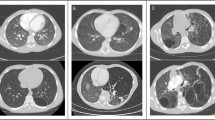

Anatomical lung volume of the fixed left lungs at 6 months after surgery of the Sham, Bilobectomy, and Pneumonectomy groups were 180.6 ± 13.1 ml, 295.4 ± 36.0 ml, and 425.4 ± 71.6 ml, respectively (Fig. 3a). The lungs of the Pneumonectomy group showed greater anatomical volumes than those of the Bilobectomy and Sham groups (Pneumonectomy vs Bilobectomy: p = 0.002, Pneumonectomy vs Sham: p < 0.001), and the Bilobectomy group had greater anatomical volumes compared to the Sham group (p = 0.006).

(a) The bar graph shows anatomical lung volume of the fixed left lungs 6 months after surgery of the Sham, Bilobectomy, and Pneumonectomy groups. (b) The representative histologic findings of residual left lungs of the Sham, Bilobectomy, and Pneumonectomy groups. Scale bar: 300 μm. (c,d) The bar graphs of the proportions of lung parenchyma (c) and the histologic parenchymal amounts (d) of the Sham, Bilobectomy, and Pneumonectomy groups. PNX: pneumonectomy.

Histologic lung parenchymal amount

Representative histologic findings of the residual left lungs of the Sham, Bilobectomy, and Pneumonectomy groups are shown in Fig. 3b. No apparent alveolar hyperinflation was observed in the Bilobectomy and Pneumonectomy groups despite the large increases in anatomical lung volume (Fig. 3b,c). There was not obvious vascular dilation in the alveolar region of the Bilobectomy and Pneumonectomy groups. The histologic parenchymal amounts of the Sham, Bilobectomy, and Pneumonectomy groups were 44.0 ± 5.0 ml, 67.6 ± 9.3 ml, and 96.5 ± 13.3 ml, respectively (Fig. 3d). The Pneumonectomy group exhibited greater histologic parenchymal amount than the Bilobectomy and Sham groups (Pneumonectomy vs Bilobectomy: p = 0.002, Pneumonectomy vs Sham: p < 0.001), and the Bilobectomy group had larger histologic parenchymal amount compared to the Sham group (p = 0.007).